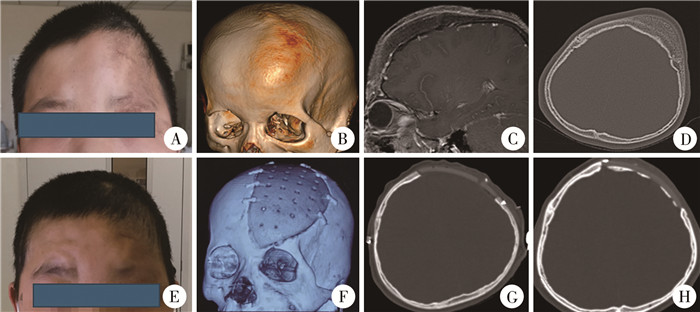

图 1 1例朗格罕细胞组织细胞增生症患儿的影像学资料 Fig.1 Imaging data of a child with LCH 注 A:术前颅脑CT轴位脑窗;B:术前颅脑CT轴位骨窗;C:颅脑MRI轴位T2;D:颅脑MRI轴位T1;E:术前颅脑CT骨窗三维重建;F:术后颅脑CT轴位脑窗;G:术后颅脑CT轴位骨窗;H:随访时颅脑CT骨窗三维重建 |

图 3 1例骨纤维结构不良患儿影像学资料 Fig.3 Imaging data of a child with OFD 注 A:术前外观,见左侧额顶及眉弓异常凸起;B:术前颅脑CT骨窗三维重建;C:术前颅脑MRI-T1增强矢状位;D:术前颅脑CT轴位骨窗;E:术后外观,见左侧额顶及眉弓形态正常;F:术后颅脑CT骨窗三维重建;G:术后颅脑CT轴位骨窗;H:随访时颅脑CT轴位骨窗 |